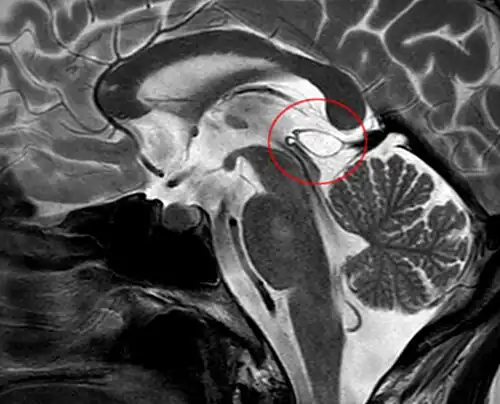

MRI axial in false color -

Another case: sagittal